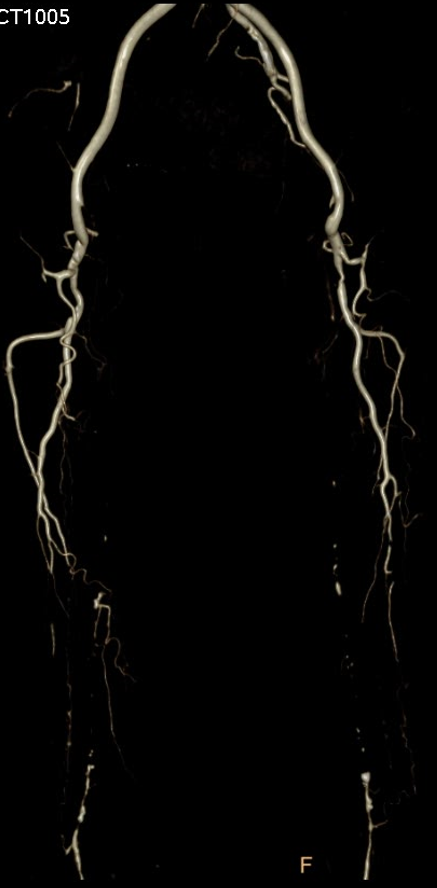

临床背景与核心挑战

股腘动脉(Femoropopliteal Artery, FPA)因其跨越髋、膝两大屈曲关节,承受复杂应力,病变常表现为弥漫性、严重钙化、慢性完全闭塞(CTO)。对于此类患者,治疗目标不仅是改善缺血症状,更强调长期通畅率(Patency),因为一旦支架内再闭塞,患者可能因侧支循环差而迅速进展至肢体威胁性缺血。

传统上,>10cm 的长段 CTO 被认为更适合旁路移植术(Bypass),因其仅在吻合口处有损伤,而桥血管本身不受干预。相比之下,全腔内治疗会对整个病变段造成全程损伤(球囊扩张、支架植入),极易诱发严重的新生内膜增生(Neointimal Hyperplasia),这是导致再狭窄的根本原因。

中心实践:15例病例随访与典型分享

DEC 策略为下肢动脉长段 CTO 病变提供了一种创新的腔内解决方案。初步15例经验表明:

其一年期通畅率值得肯定,部分病例甚至实现了两年以上的完美通畅;

能有效克服夹层、recoil 和内膜增生等核心难题;

但仍需关注并发症(如远端栓塞、假性动脉瘤)及患者依从性。

尽管一期费用偏高,但从长期保肢和减少再干预的角度看,其卫生经济学价值值得期待。未来,随着更多病例的积累和长期随访数据的完善,DEC 理念有望成为处理此类复杂病变的重要选择。